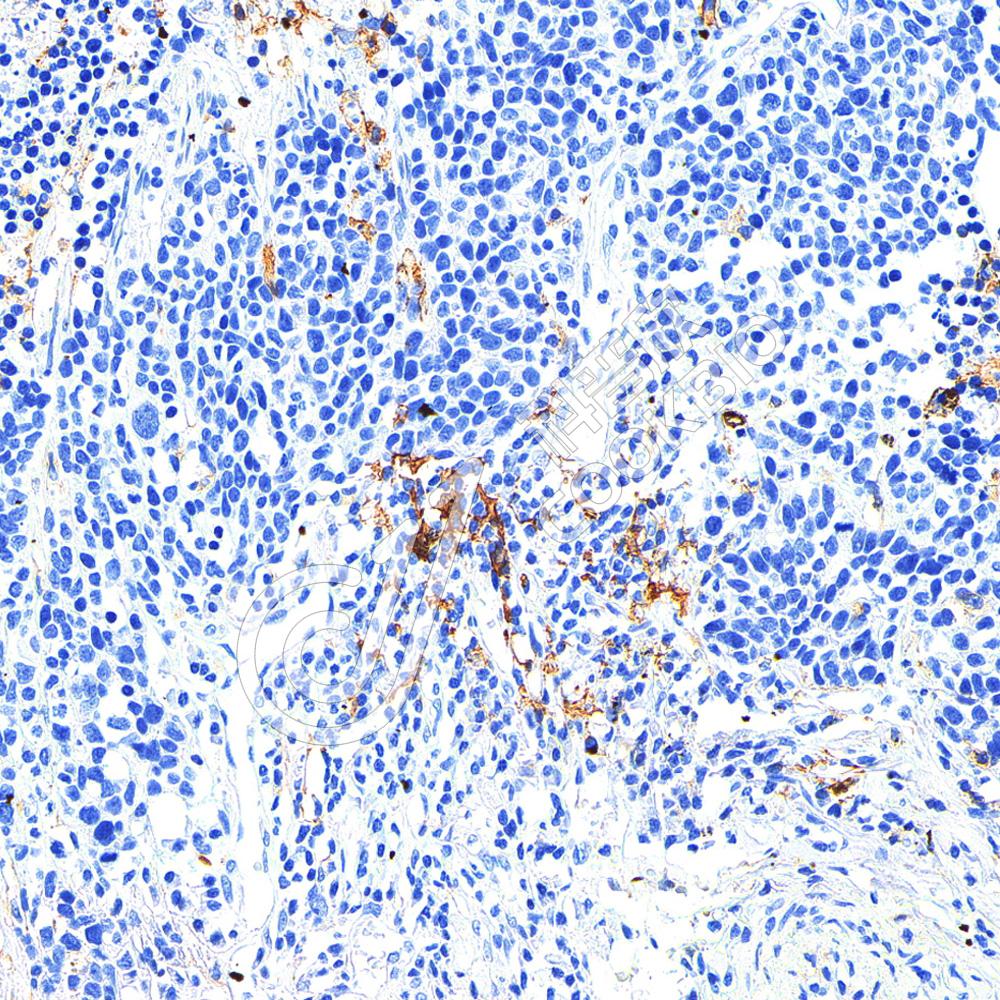

IHC检测CD11c蛋白(货号 K236177).

样品: 人小细胞肺癌, 4%多聚甲醛 (货号KSG1101) 固定12-24小时.

抗原修复: 柠檬酸抗原修复液(干粉, pH 6.0) (KSG1201), 高压锅均匀喷气计时2分钟.

—抗: 1: 1000稀释, 4℃ 孵育过夜.

二抗: S-vision免疫组化多聚二抗(山羊抗小鼠), 即用型(货号KB3903), 室温孵育20分钟.